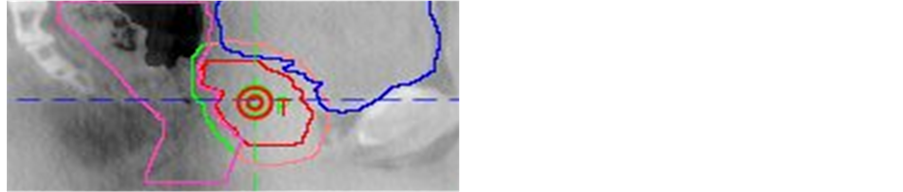

The rescans of CBCT for large offset were performed in 113 (5%) of 2302 fractions and in 41 (67%) of 61 patients. The causes for CBCT rescans are listed in Table 1. After the first rescan, the large offset was resolved in 106 (94%) of 113 fractions (Figure 1). For the remaining 7 fractions, a second rescan was performed in 4 fractions for persistent large offset, three rescans were needed for 2 fractions, and four rescans were used for 1 fraction. The details of the numbers of CBCT rescans per patient are as follows; 0 in 20 (33%) patients, 1 - 3 in 29 (48%) patients, 4 - 7 in 10 (16%) patients, and 8 - 10 in 2 (3%) patients. Figure 2 shows the distribution of the CBCT rescans during all 38 fractions of IMRT.

Figure 1. A case with severe misregistration caused by excess rectal gas. The red line is the CTV, pink line is PTV, the purple line is the rectum and the blue line is the bladder on the planning CT. (a) Severe misregistration with excess rectal gas is shown in a fused image consisting of the planning CT and initial CBCT image. (b) Severe misregistration was resolved after the discharge of the rectal gas as shown in a fused image consisting of the planning CT and rescan CBCT image.